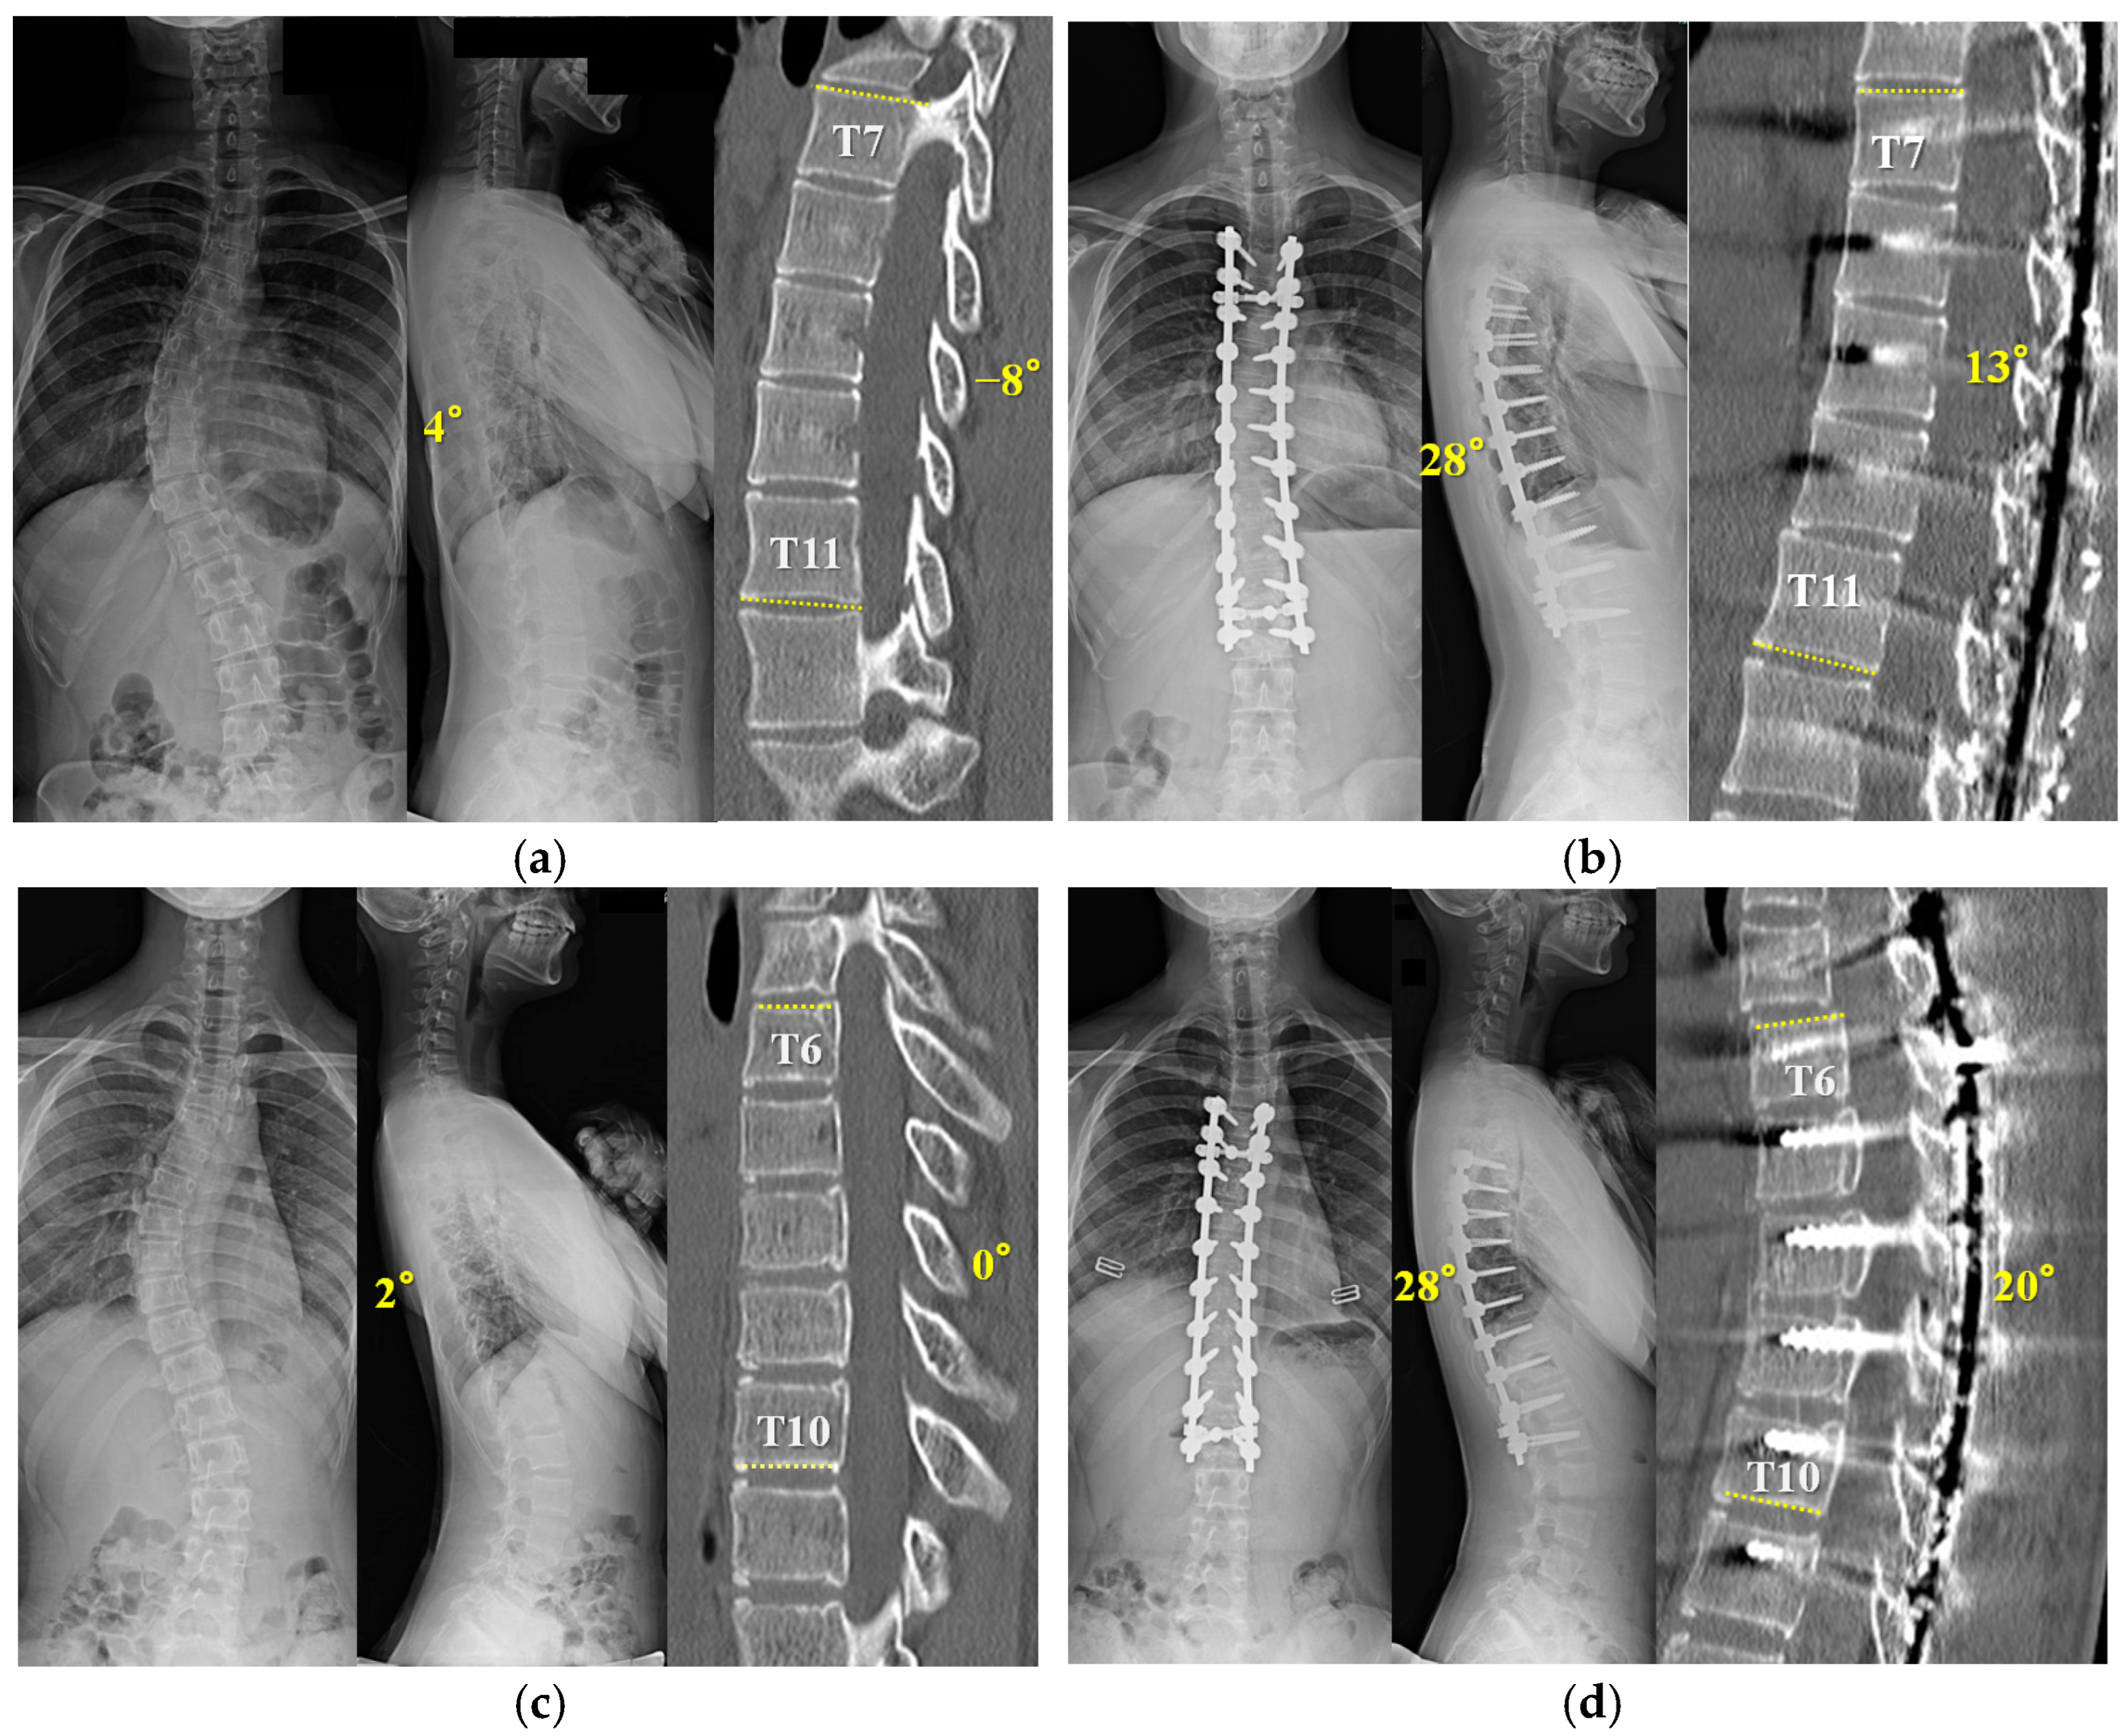

3.6. Representative Cases in RR with Outrigger Device

A fifteen-year-old girl with Lenke 1A- was used as the representative case (Figure 5a,b). (a) A preoperative X-ray showed thoracic hypokyphosis of 4°. Apical five vertebral kyphosis was −8 degrees. (b) She underwent T4-L2 posterior spinal fusion surgery with concave RR and convex DRC using the outrigger. After the apical setscrews were tightened (T7–11), segmental DVR for thoracolumbar curve-correction was performed from T11 to the lowest instrumented vertebra (L2). After surgery, TK increased to 28°. Next, a thirteen-year-old girl with Lenke 1B- was shown (Figure 5c,d). A preoperative X-ray showed thoracic hypokyphosis of 2°. She was found to have six non-rib-bearing vertebrae (L1–6). Apical five vertebral kyphosis was 0 degrees. (b) She underwent T5-L2 posterior spinal fusion surgery with concave RR and convex DRC using the outrigger. After the apical setscrews were tightened (T6–10), segmental DVR for thoracolumbar curve correction was performed from the caudal neutral vertebra (T12) to the lowest instrumented vertebra (L2). After surgery, TK was increased to 28°.

Figure 5.

The X-ray and CT show a fifteen-year-old girl with Lenke 1A- scoliosis (a,b), and a thirteen-year-old girl with Lenke 1B- (c,d). (a) Preoperative X-ray shows a Cobb angle of 48° and 4° of TK. Apical five vertebral kyphosis is −8 degrees. (b) Postoperative X-ray shows a Cobb angle of 5°and 28° of TK after posterior fusion and correction using the outrigger. Apical five vertebral kyphosis is improved by 13 degrees. (c) Preoperative X-ray shows a Cobb angle of 51° and 2° of TK. Apical five vertebral kyphosis is 0 degrees. (d) Postoperative X-ray shows a Cobb angle of 5°and 28° of TK after posterior fusion and correction using the outrigger. Apical five vertebral kyphosis is improved by 20 degrees.